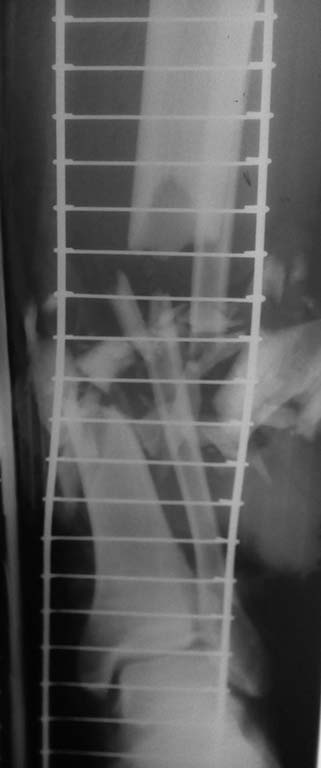

Поступил пациент с открытым (тип IIIВ по Gustillo-Andersen) переломом костей голени.

Травма на производстве 17.05.16 – на ногу упал тяжелый кусок кирпичной стены.

После короткой предоперационной подготовки 17.05.16 пациенту в условиях операционной произведена повторная ревизия раны с удалением нежизнеспособных мягких тканей, свободных фрагментов большеберцовой кости. Во время тщательного дебридмента выявлено обширное размозжение кожи и подкожной клетчатки по передней, внутренней и наружной поверхностям правой голени, значительное повреждение мышц передней, наружной групп мышц с дефектом мышечной ткани, менее значительным оказалось повреждение задней группы мышц правой голени. Во время дебридмента определено значительное повреждение поверхностного и глубокого малоберцового нервов. Укорочение правой большеберцовой кости составило ~9 см.

Выполнено острое укорочение малоберцовой и большеберцовой костей с опилом торцов основных отломков и последующим укрытием области перелома мышечными пластами. Наложен стержневой аппарат наружной фиксации (три стержня Штеймана установлены в прокисмальный отломок и три – в дистальный отломок). С целью дренирования установлены полутрубчатые выпускники. Ушивание кожи без натяжения. После выполнения операции произведена оценка сосудистого статуса дистальной части правой голени и правой стопы. Капиллярная реакция сохранена (2 сек), пульсация на задней большеберцовой артерии определяется. Пульсация на тыльной артерии стопы не определяется. В послеоперационном периоде пациент переведен в отделение реанимации для проведения интенсивной терапии.

Ds: Открытый многооскольчатый перелом (тип IIIВ по Gustillo-Andersen) нижней трети диафизов обеих костей правой голени со смещением отломков, дефектом костного вещества, дефектом мягких тканей, повреждением переднего сосудисто-нервного пучка правой голени, повреждением ветвей малоберцового нерва на уровне средней-нижней трети правой голени.